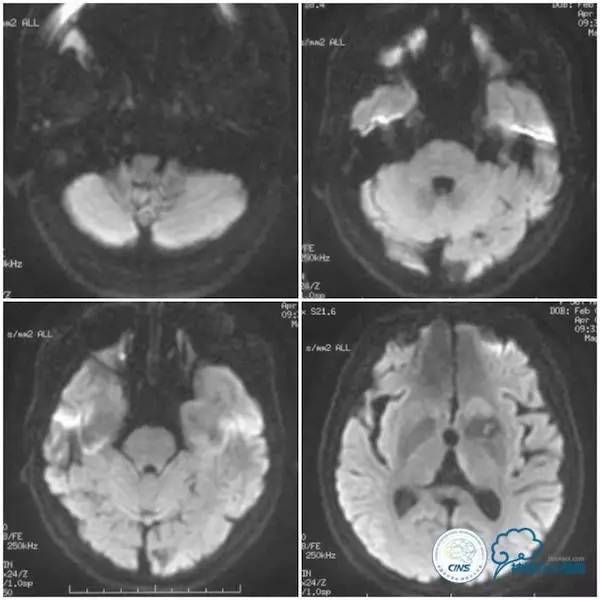

患者,女,56岁,主因“发作性头晕伴行走不稳1个半月”入院。患者1个半月前无明显诱因突发头晕,伴行走不稳,左下肢踩棉感,偶伴有恶心、呕吐。头晕与体位有关,站立行走时出现,平卧及坐位可减轻,无复视、耳鸣、肢体麻木无力、意识障碍等,后就诊于当地医院,查头颅MRI示后循环区域未见新近梗死,左尾状核头及侧脑室前角区域陈旧性脑梗死(图1)。

图1